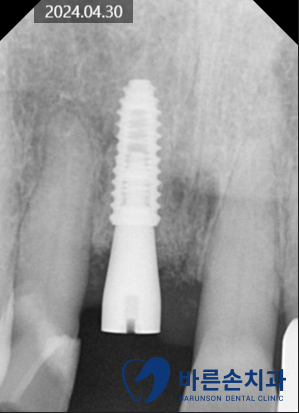

23.10.18

위 앞니가 아프고 시려 내원하신 분입니다.

환자분의 치아 상태를 확인해보니

앞니의 치경부 (치아와 잇몸 경계) 부분에

충치가 많이 진행되어 있습니다.

충치가 너무 깊어서

살릴 수 없는 치아는 임플란트 하고

살릴 수 있는 두개 치아는

신경치료+크라운 하기로 했습니다.

충치가 깊지 않은 치아는

레진으로 간단하게 때우기로 합니다.

가장 많이 썩은 치아는

발치하는 동시에 임플란트 식립을 하였습니다.